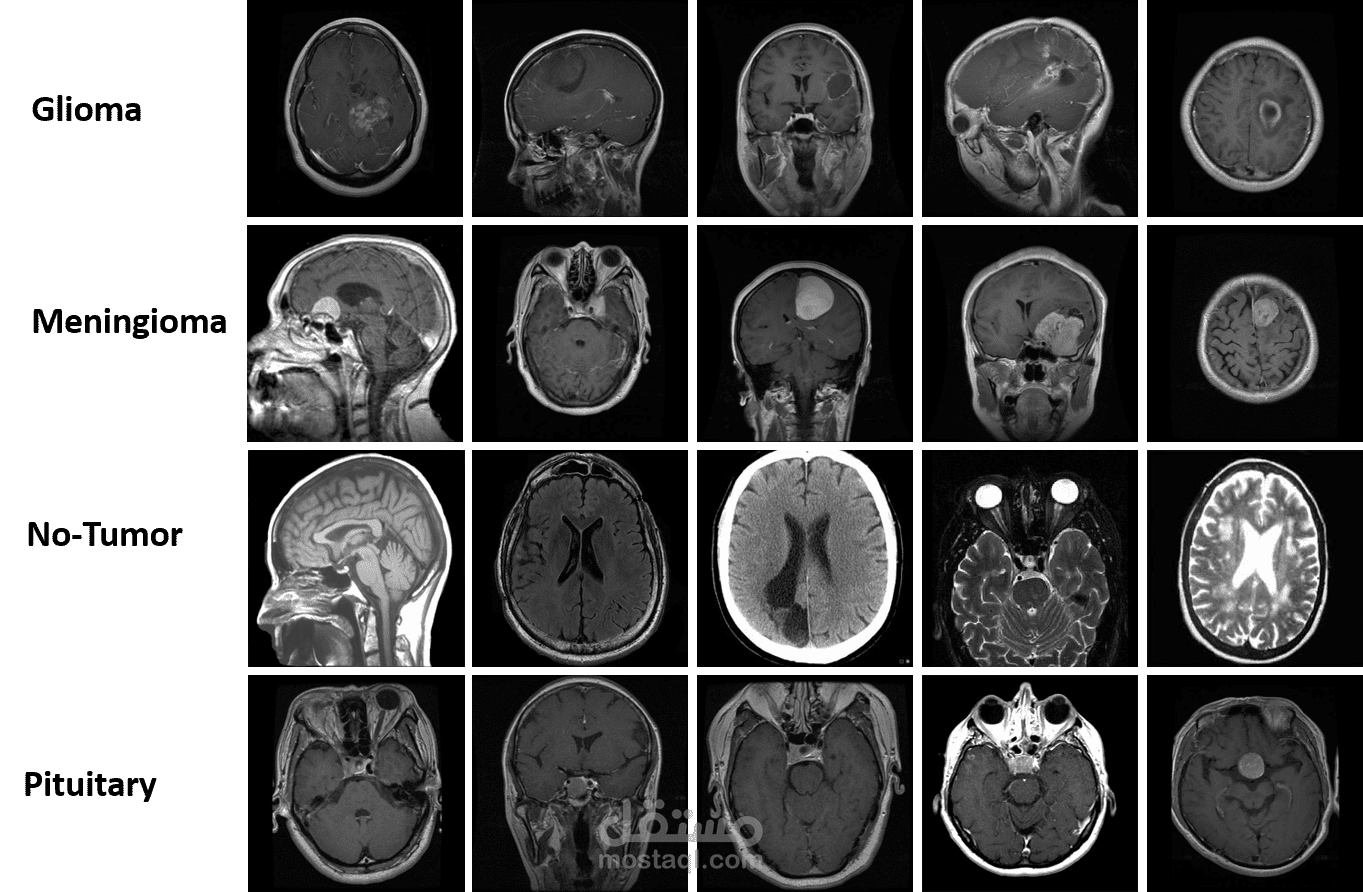

يهدف هذا المشروع إلى تطوير نموذج ذكاء اصطناعي يعتمد على الشبكات العصبية التلافيفية (CNN) و التعلم المنقَّل (Transfer Learning) لتصنيف صور الأشعة الدماغية (MRI) إلى فئات مختلفة مثل الأورام الحميدة، الأورام الخبيثة، أو الأنسجة السليمة.

المخرجات: نموذج دقيق لتصنيف الأشعة مع تقارير تحليلية وإمكانية نشره لاستخدامه في التشخيص الطبي.